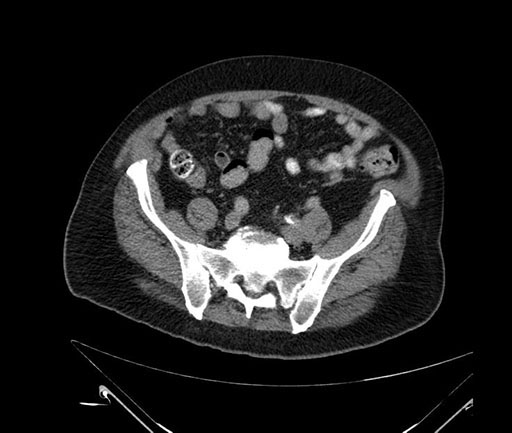

Whipple (pancreaticoduodenectomy) [case 7]

Imaging Analysis

Look through the patient's CT scan to identify any areas of concern for the necessary procedure.

Based on your CT findings, which issue(s) would give reason for "planned slowing down moment(s)" in this case?

Considering a standard Whipple procedure, what step(s) of the operation would you do differently in this case?